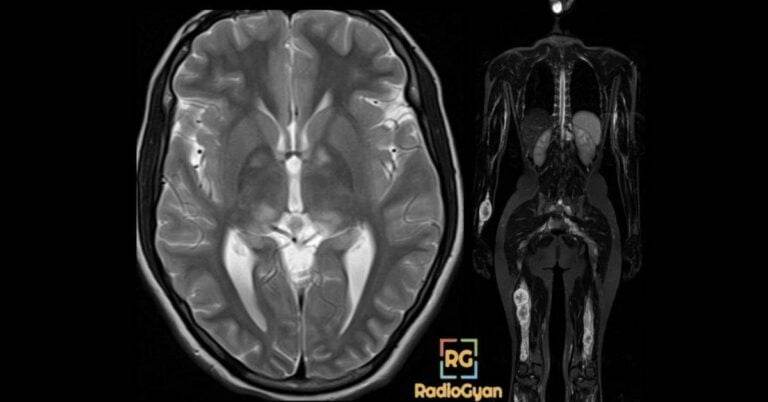

Neurofibromatosis (NF) – ALL You Need to Know!

Neurofibromatosis imaging primer for clinicians: NF1/NF2, diagnostic criteria, and key radiology signs to aid diagnosis.